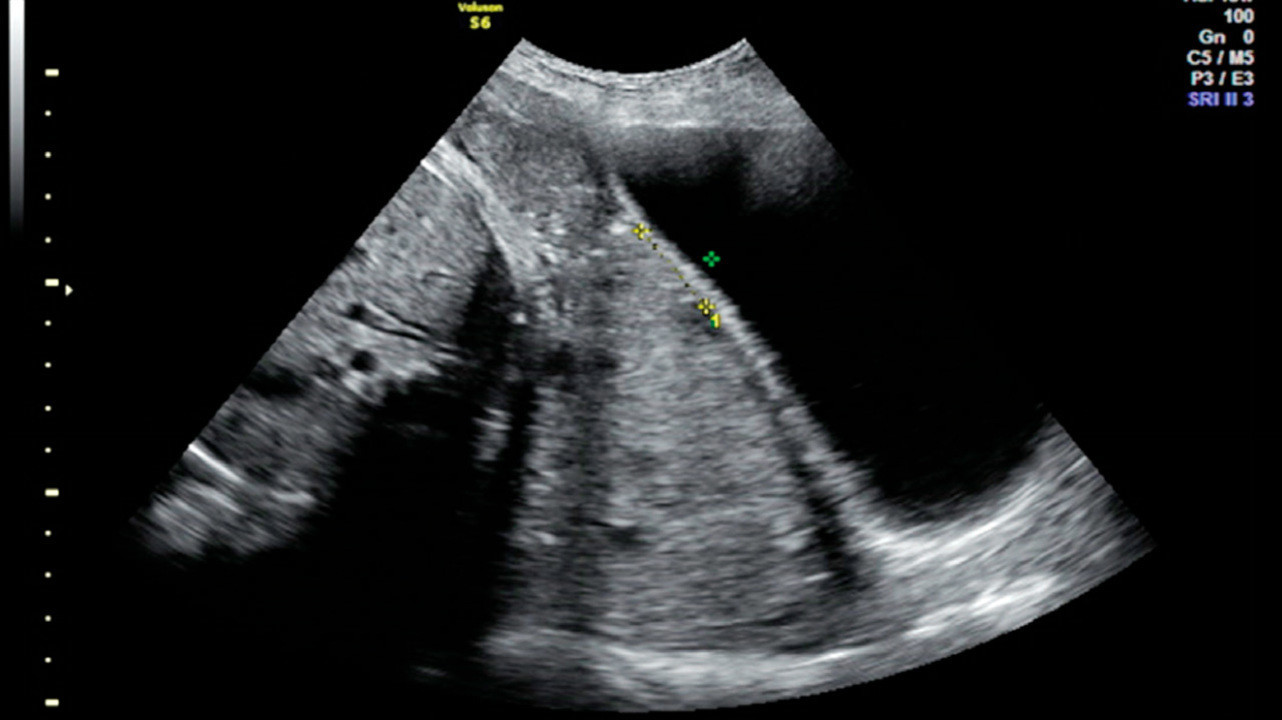

- Данные инструментальных методов исследования — трансабдоминальное/трансвагинальное УЗИ. Позволяет установить факт предлежания плаценты и получить объективные данные о варианте предлежания плаценты, оценить площадь, структуру, размеры и степень зрелости плаценты, степень отслойки, наличие ретроплацентарных гематом, выявить «миграцию плаценты» и ее динамику.

Место прикрепления

Определяется с помощью УЗИ. Как было сказано выше, при нормальной беременности плацента располагается в теле матки. Иногда при ультразвуковом исследовании в первой половине беременности обнаруживается, что плацента располагается в нижних отделах матки, доходя или даже перекрывая область внутреннего зева шейки матки. В дальнейшем, по мере прогрессирования беременности, плацента чаще всего смещается из нижних отделов матки верх. Однако, если после срока 32 недели плацента по-прежнему перекрывает область внутреннего зева, такое состояние называется * предлежанием плаценты**, что является серьезным осложнением беременности.

Степень зрелости

Этот параметр, как говорят врачи, «ультразвуковой», то есть он зависит от плотности определяемых при ультразвуковом исследовании структур плаценты.

Различают четыре степени зрелости плаценты:

- В норме до 30 недель беременности должна определяться нулевая степень зрелости плаценты.

- Первая степень считается допустимой с 27 по 34 неделю.

- Вторая — с 34 по 39.

- Начиная с 37 недели может определяться третья степень зрелости плаценты.

В конце беременности наступает так называемое физиологическое старение плаценты, сопровождающееся уменьшением площади ее обменной поверхности, появлением участков отложения солей.